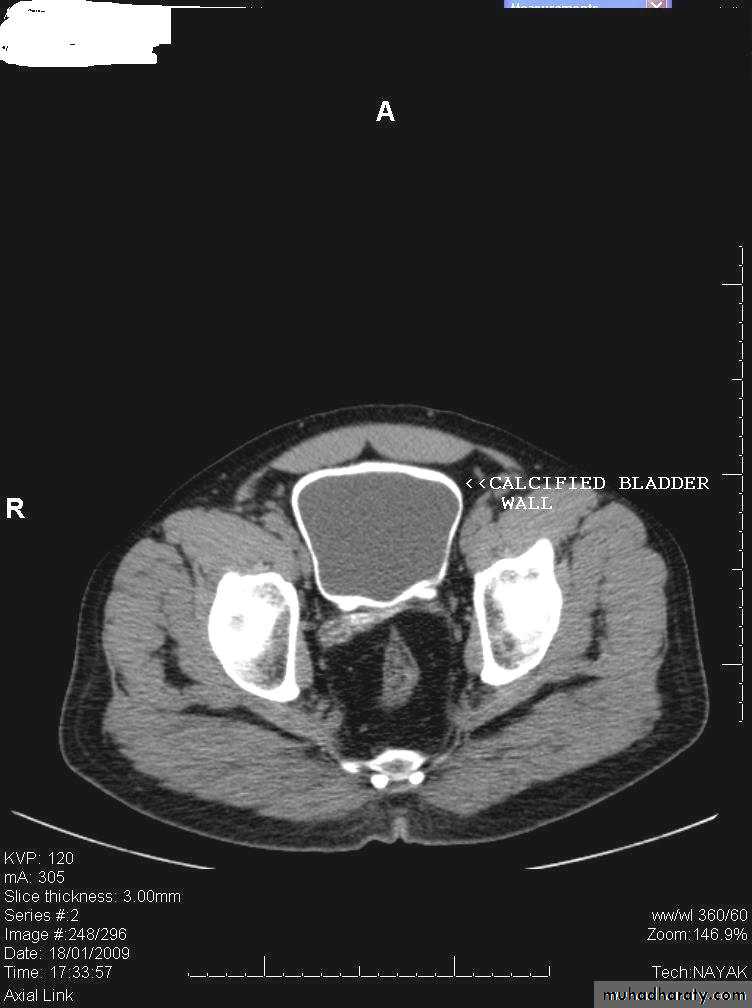

• Bladder calcification

• The most frequent cause of calcification is calculi ( large and laminated). Calcification in the wall is rare and usually due to schistosomiasis or bladder tumor.• Urinary bladder infection

• Tuberculosis: it is always associated with renal TB. It produce irregular wall thickening and decrease in bladder capacity due to fibrosis (thick contracted bladder). Calcifications is present in 10% of cases and could be seen on plain film and CT

Schistosomiasis: US may be normal at early stage, latter will show wall thickening(up to 1 cm or more) and multiple polypoidal lesions. Latter on calcification may develop which appear on plain film in 50% of cases as egg shell or linear calcification in the bladder wall and lower ureters. In contrast to TB, the bladder capacity and contractility is well preserved. The condition predispose to squamous cell carcinoma due to epithelial metaplasia.